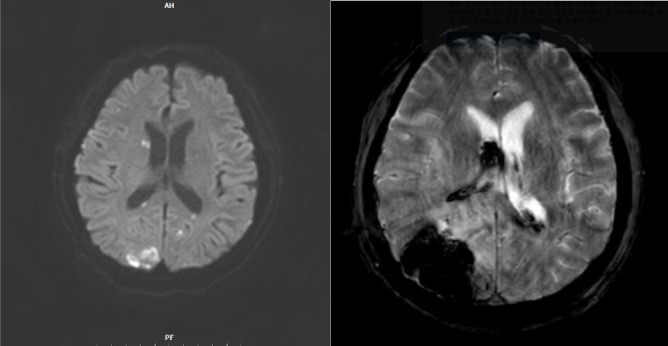

Septic embolism and stroke are serious complications in patients with sepsis and often necessitate urgent surgical intervention to control the source of infection. A 69-year-old man presented with severe pain in his back and left thigh. MRI revealed extensive posterior epidural or subdural abscesses extending from the cervical to the lumbar level, as well as an abscess in the iliopsoas muscle. The patient underwent urgent drainage of the abscesses and decompression of the lumbar spine. Postoperatively, he developed sudden-onset atrial fibrillation and altered mental status. Brain CT showed multiple embolic infarctions. His condition deteriorated due to persistent infection, leading to disseminated intravascular coagulation, acute kidney injury, and septic shock. This case highlights the risk of cerebral embolism and hemorrhagic complications in patients with sepsis who undergo surgery. Early recognition of individuals at high risk and comprehensive perioperative management are critical to reducing the likelihood of such complications.